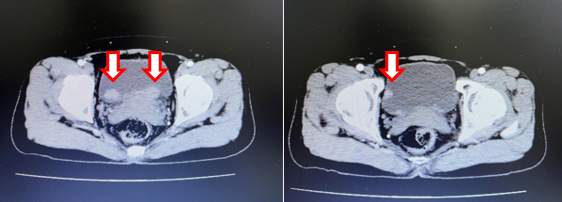

- Cắt lớp vi tính ổ bụng:

Hình 6: Cắt lớp vi tính ổ bụng (16/06/23): không thấy các tổn thương thứ phát tại bàng quang (mũi tên)

Hình 7: Cắt lớp vi tính ổ bụng (16/06/23): Hình ảnh u máu gan phải, khối lớn nhất kích thước 35x38mm (không thay đổi đáng kể so với phim cũ 06/2022) (mũi tên)

Hình 8: Cắt lớp vi tính ổ bụng (06/03/24): Không thấy hình ảnh u cục, tổn thương thứ phát tại bàng quang (mũi tên)

Hình 9: Cắt lớp vi tính ổ bụng (06/03/24): Hình ảnh u máu gan phải, khối lớn nhất kich thước 36x52mm (mũi tên)